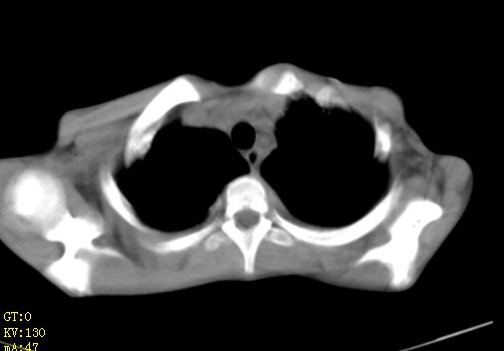

女,12岁,气促、咳嗽2天,3个月前查胸片示:两肺感染,急诊入院查ct,血常规等未检查。

双肺中下野不规则片絮状阴影,中外带明显,双侧胸腔少量积液,心影增大,心腔密度减低,隆突下及左侧气管旁见钙化淋巴结影,考虑双肺感染、心衰;建议结合临床除外h1n1并急性心衰,先心不能排除。

两肺多发片絮状模糊影,以下肺外带居多,内见支气管气像,纵膈窗未减影,两侧胸腔积液,心影增大,结合心超,支持重症肺炎,非常时期,甲型h1n1流感不排除。